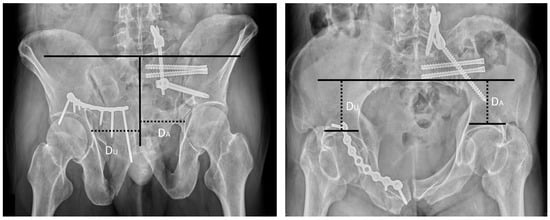

| Sagi et al., 2009 | Inlet and outlet ratio Method (Sagi Method) [11] | On the inlet view, we drew a line across the anterior border of the sacrum, perpendicular to the spinous processes. The perpendicular distance from this line to the subchondral bone of each acetabulum was measured, and a ratio was then calculated, with the affected side of pelvis set as the numerator. A similar ratio was obtained for the outlet view by drawing a line parallel to the superior end plate of S1, perpendicular to the spinous processes. The perpendicular distance from the reference line to the subchondral bone of each acetabulum was measured, and a ratio was then calculated, with the affected side of pelvis set as the numerator (Figure 3). |